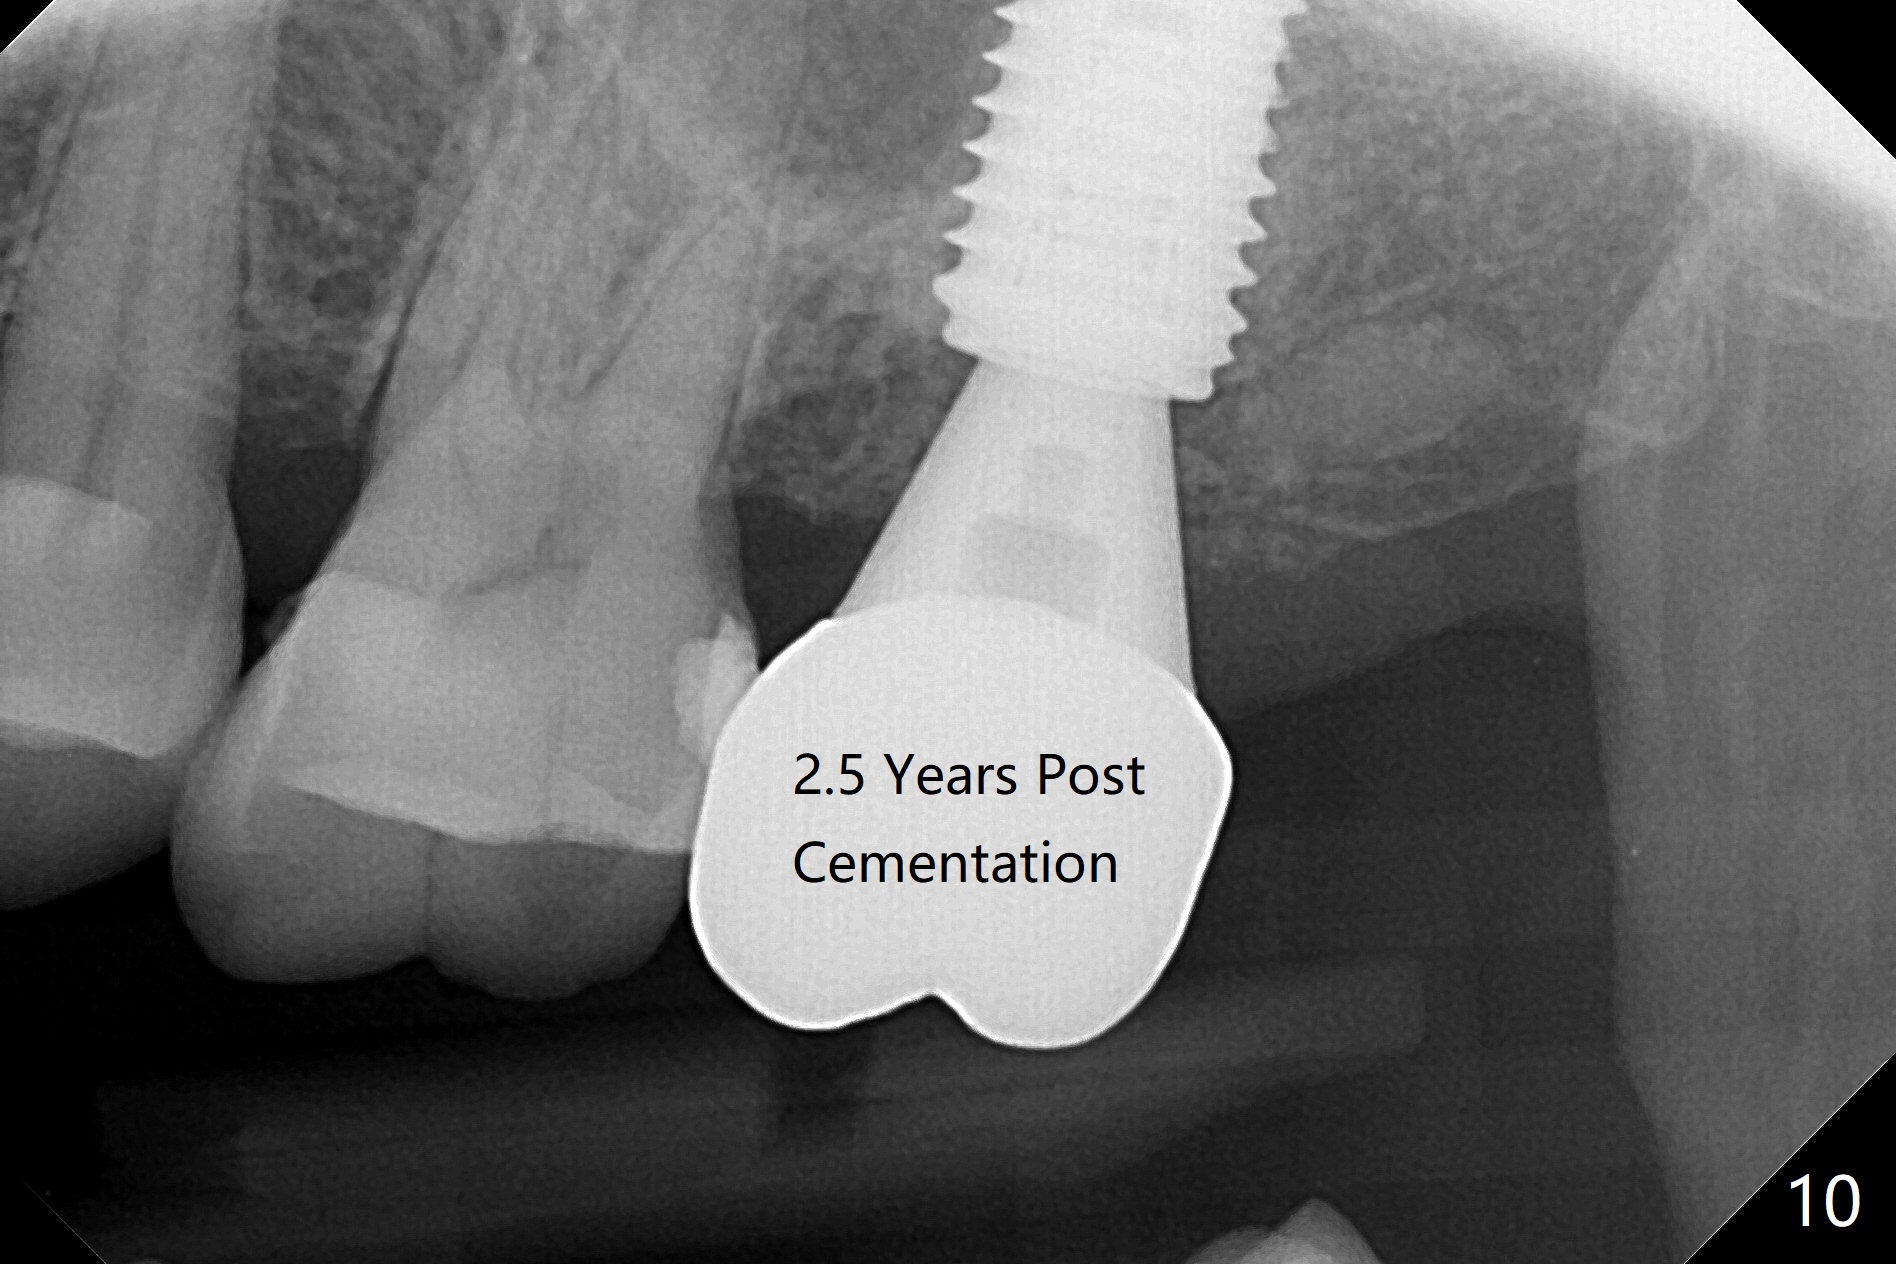

While the tooth #2 has a mesiodistal crack line with symptom (Fig.1 arrowheads, crown pending), the tooth #15 has a mesiodistal fracture (Fig.2). Immediately preop 5x5 cm CBCT (Fig.3) confirms the palatal (P) fracture with palatal bone loss. Although a 5x7.3 mm implant fits the site by design (Fig.4), a much longer implant is required to achieve primary stability past the sinus floor using IBS Magic Expanders (Fig.5,6 (20-30 Ncm; sinus lift with PRF membrane and allograft)). In contrast, primary stability could not be obtained by engaging dummy implant to the socket walls. A short implant without sinus lift is associated with less obvious complication such as fibrointegration. The implant seems osteointegrated 4.5 months postop (Fig.7). The abutment is changed to 6.5x4(5) mm before impression. There is no bone loss 5 months post cementation (Fig.8 (11 months postop)). It is the same 2.5 years post cementation (Fig.9,10).